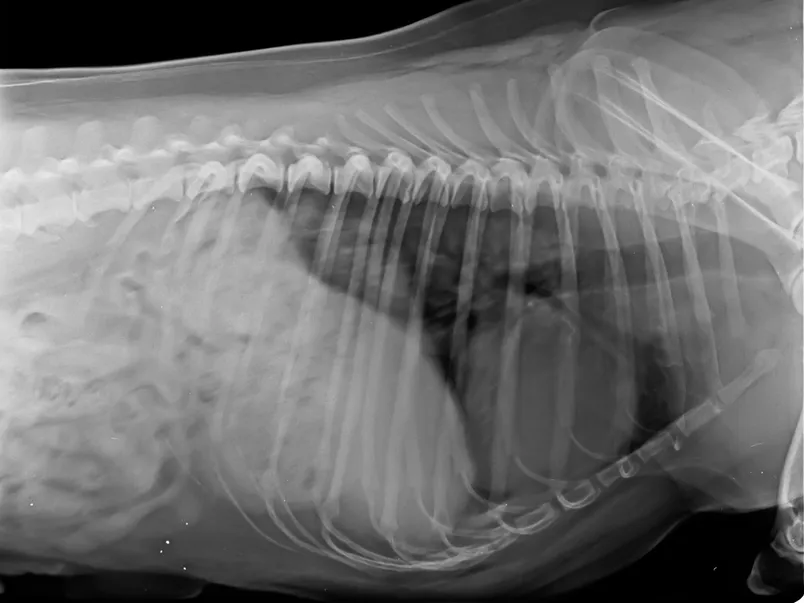

Digital Radiography (X-Rays)

Digital X-rays provide detailed images of your pet’s bones, organs, and chest or abdominal cavity. They are quick, safe, and offer high-quality results with minimal stress. We commonly use X-rays to diagnose:

• Fractures or injuries

• Arthritis and joint concerns

• Heart and lung abnormalities

• Gastrointestinal blockages

• Organ enlargement or changes